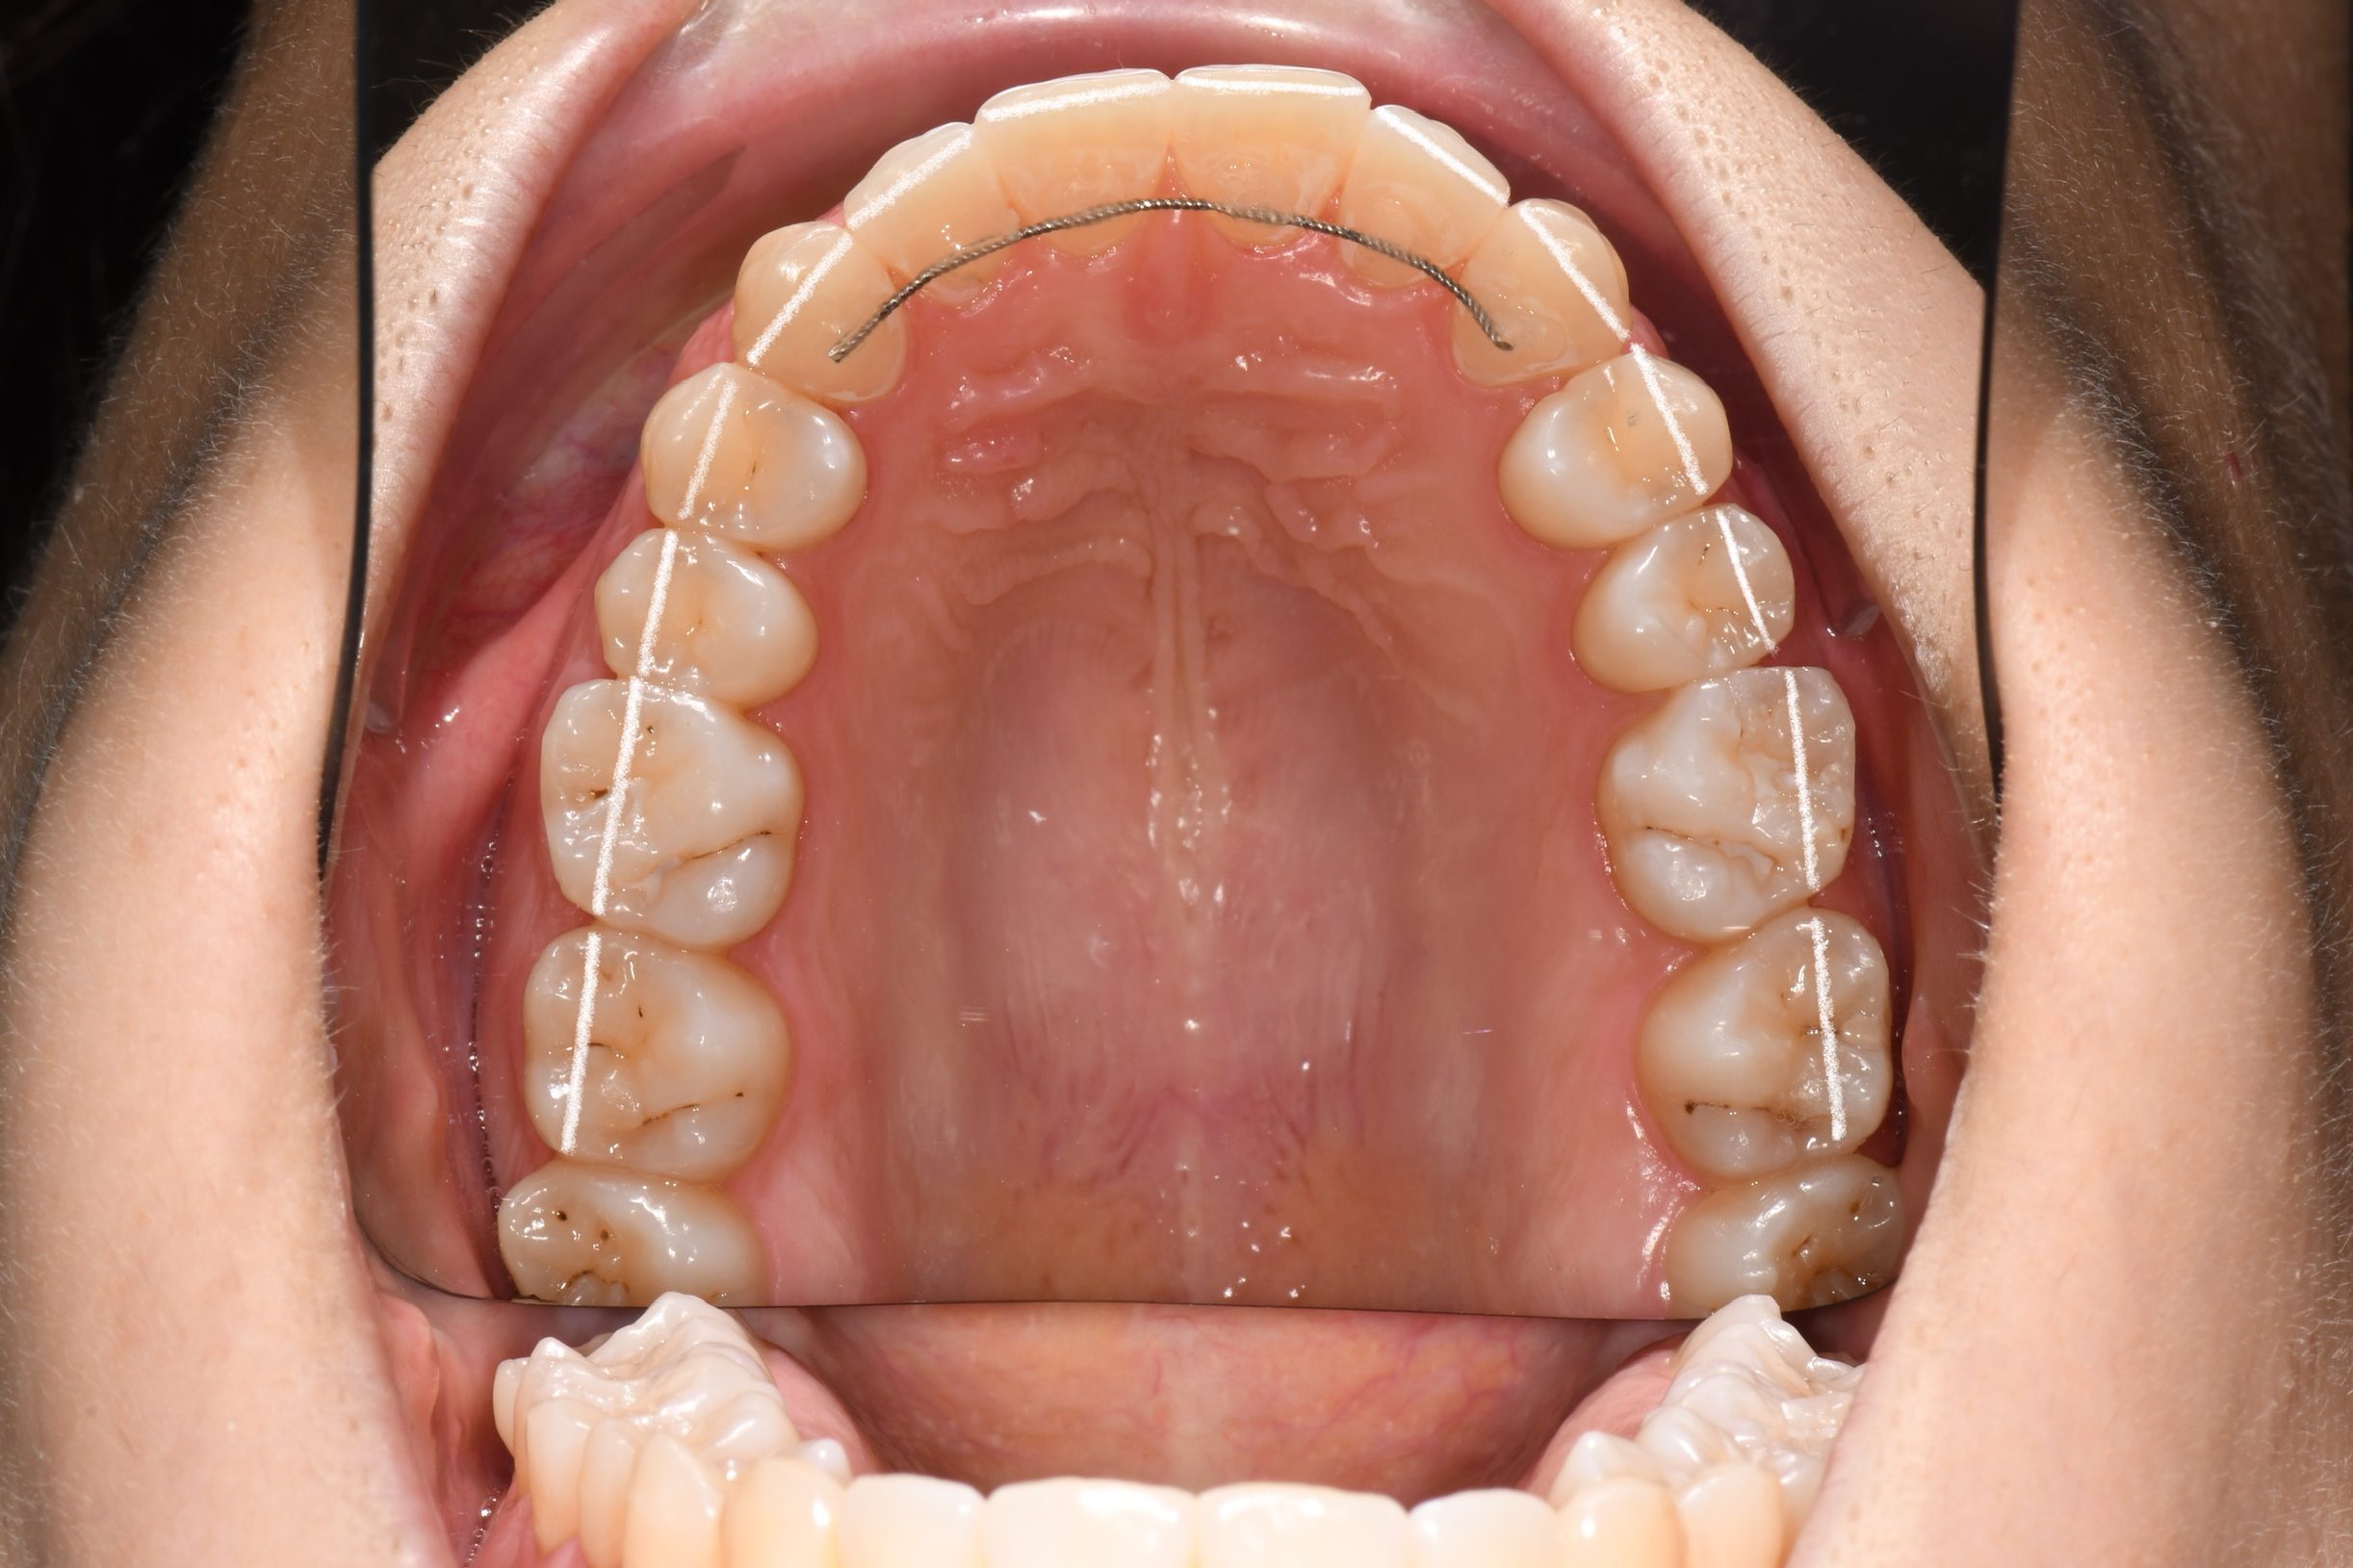

Az elmúlt évekből rengeteg szakmai referenciát tudnánk bemutatni, amelyek különböző fogszabályozási problémákat oldottak meg. Válogatva a több száz esetből, ezen az oldalon olyan képeket, információkat igyekeztünk bemutatni, amelyeknek a segítségével a jövőbeni pácienseinknek azt tudjuk üzenni: A Te fogsorod is lehet gyönyörű!

(Képeket a Pácienseink külön írásos beleegyezésével mutatjuk be!)